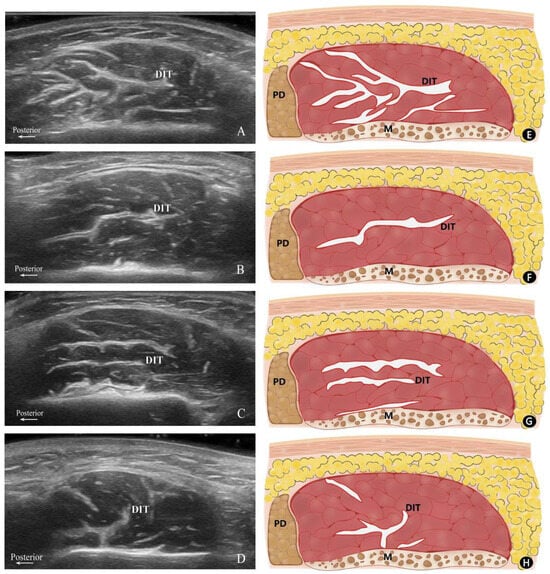

2.2. Classification of DIT Patterns